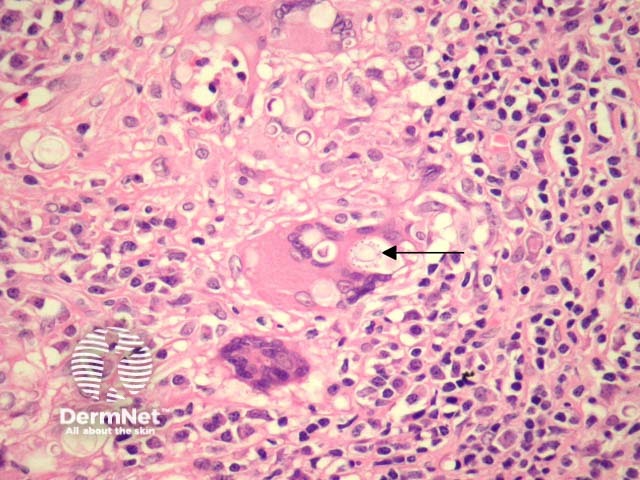

Higher power examination reveals large round fungal forms. There may be numerous eosinophils. The characteristic feature of this organism is the presence of multiple minute narrow-based buds surrounding the large round fungal forms. These have often been referred to as 'captain wheels' (figure 2, 3; arrows highlight the 'captain wheel' formation).

Figure 2

Blastomycosis – the fungal forms of blastomycosis are similar in size but have a thicker wall and do not exhibit the 'captain wheel' budding formation (figures 2, 3, arrows). Rather, they exhibit broad-based buds.